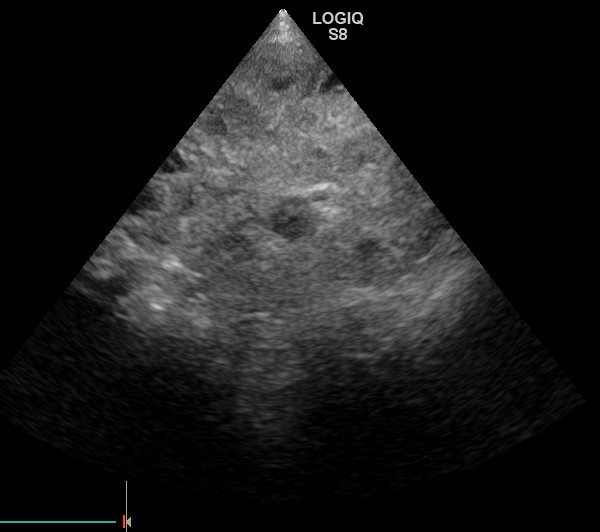

超音波検査で脾臓に大きな腫瘍が認められた為、当日に摘出手術を行いました。

超音波検査所見(写真上)脾臓に黒いボコボコした腫瘍が認められます。